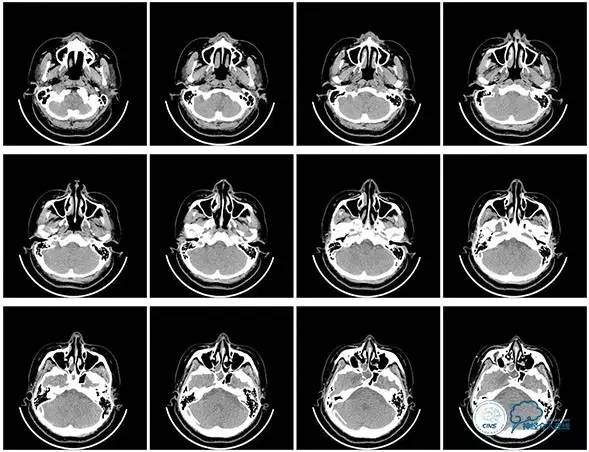

头颅CT

头颅CT(2017.6.20)

颞骨CT(2017.6.20)

2016-06-03 CT

2017-06-07 CT

术后头颅CT